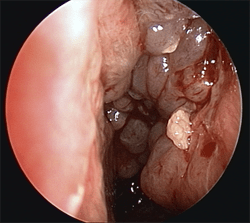

Sinusitis From A Tooth Infection Warning Graphic Medical Images Dr Gan Eng Cern